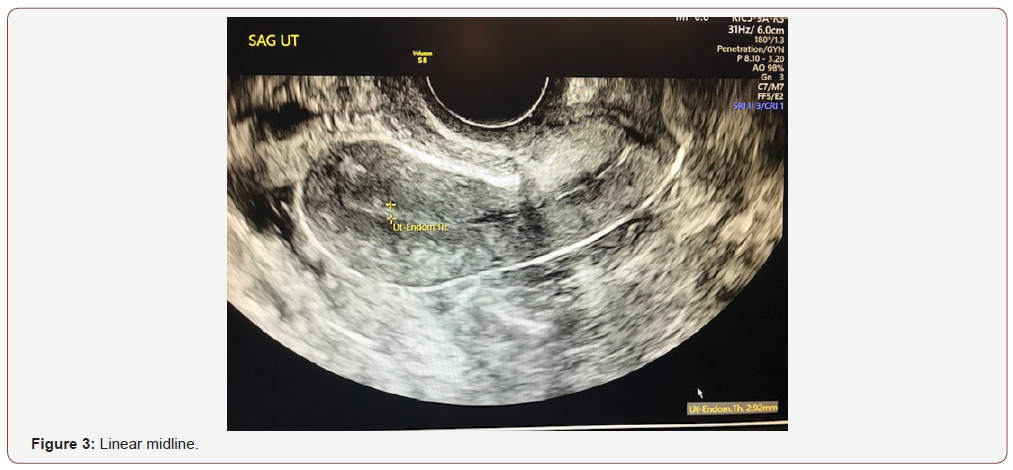

An evaluation of endometrial morphology included an assessment of endometrial echogenicity, the endometrial midline and the endometrial-myometrial junction. A ‘uniform’ endometrium included the three-layer pattern (Figure 1), as well as a homogenous hyperechogenic, hypoechogenic and is echogenic endometrium. The echogenicity is defined as ‘non-uniform’ if the endometrium appears heterogenous, asymmetrical or cystic (Figure 2). The endometrial midline was defined as ‘linear’ (Figure 3), if a straight hyperechogenic interface within the endometrium is visualized, as ‘non-linear’ if a waved hyperechogenic interface is seen, and as ‘irregular’ or as ‘not defined’ in the absence of a distinct interface (Figure 4). All studies were performed at the AIUM certified sonographic unit.